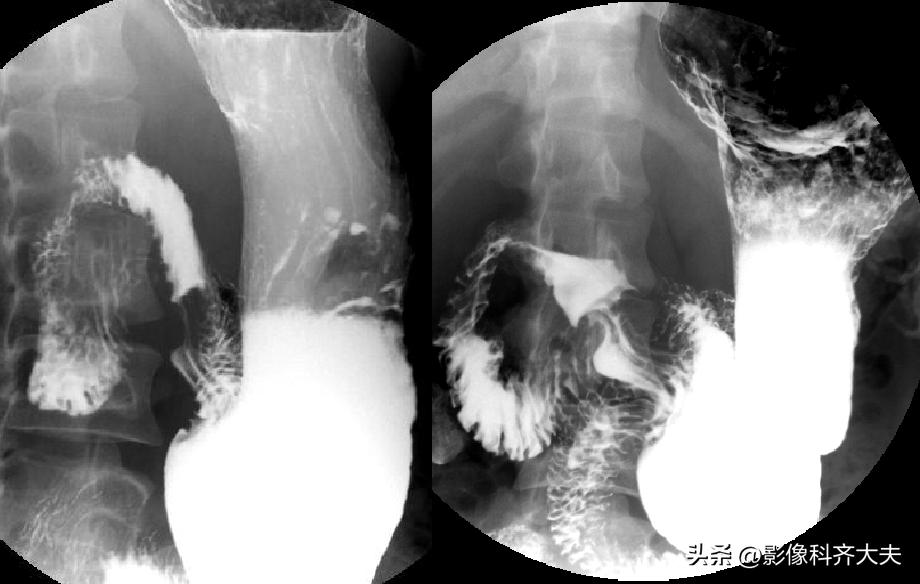

胃体、胃窦充盈相(俯卧位)

胃底、贲门双对比相(右前斜位)

胃底、贲门双对比相(左前斜位)